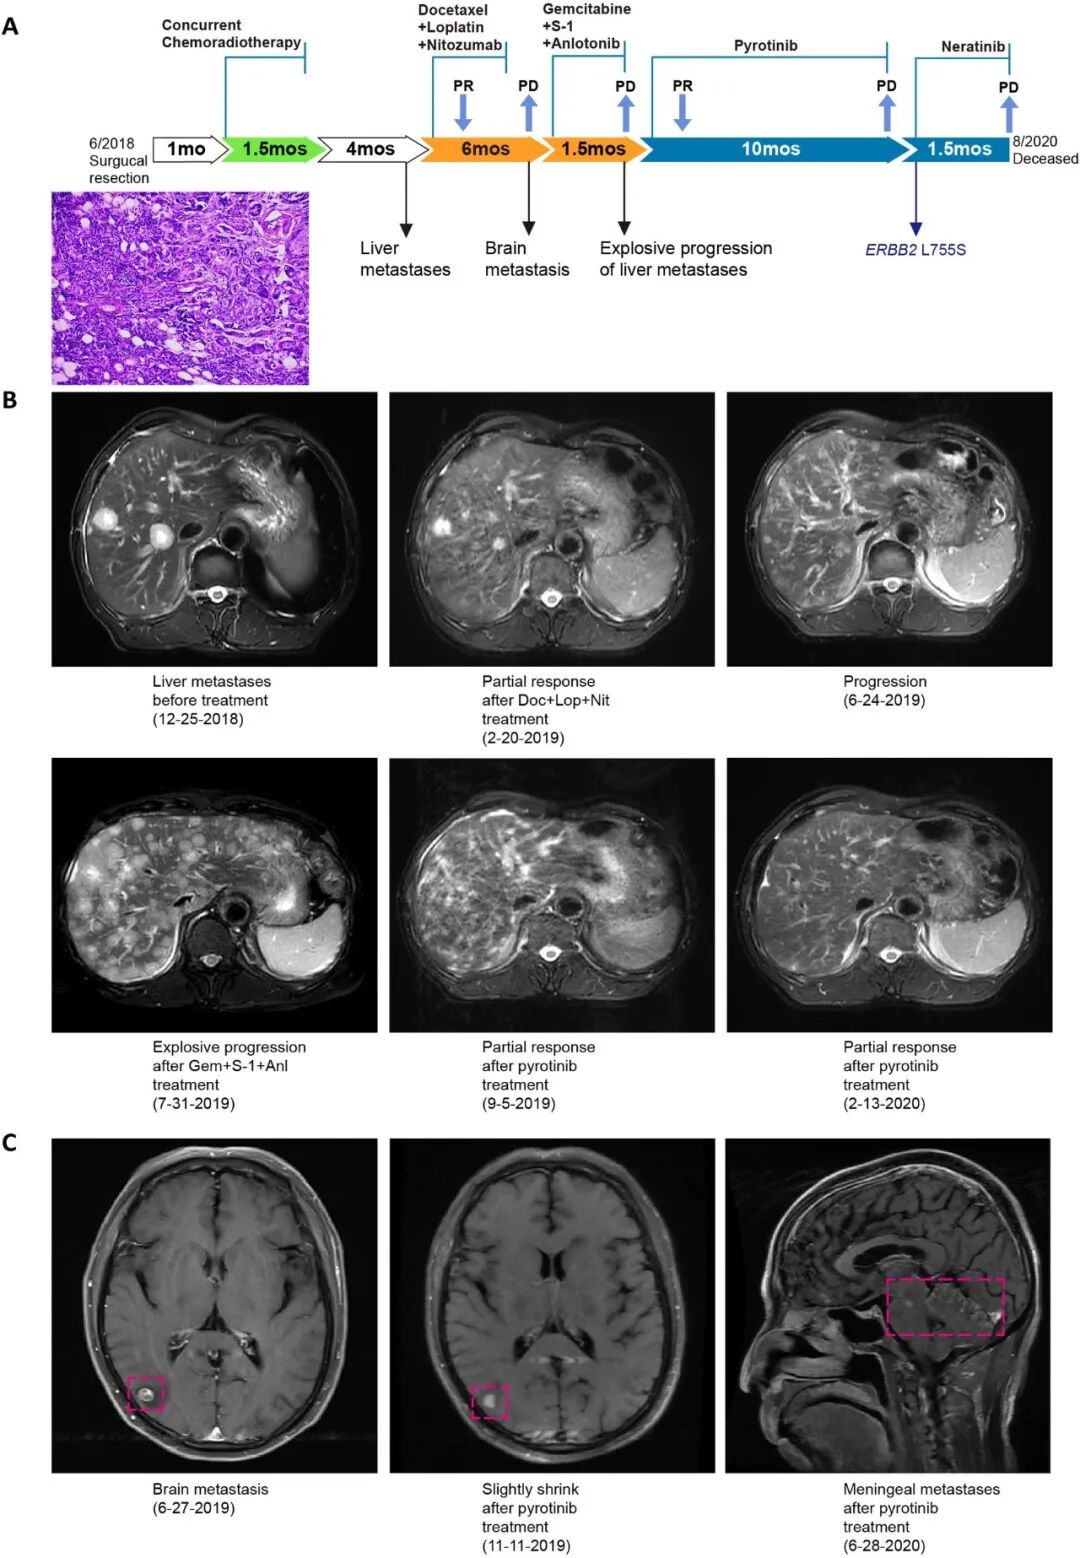

病例1:患者为62岁男性,初诊确诊为ⅣA 期涎腺导管癌,术后进行放化疗治疗。先后出现肝转移及新发脑转移和肝转移,提示疾病进展,更换化疗方案。后续发现患者肝转移灶进展加速,且出现肝功能损伤,化疗失败。NGS基因检测显示HER2扩增(扩增倍数5.3)。接受HER2酪氨酸激酶抑制剂吡咯替尼治疗1个月后,肝转移灶达到部分缓解,脑转移灶略有缩小;经积极保肝治疗后,肝功能恢复正常治疗期间,仅出现2级腹泻,耐受性良好。2020年患者发现新发脑膜转移,提示疾病进展。对患者外周血循环肿瘤DNA(ctDNA)进行基因组检测,结果显示HER2扩增(扩增倍数2.61)及 HER2 L755S突变(变异等位基因频率13.43%)(图 2)。

因临床前研究表明,HER2 L755S突变对曲妥珠单抗和HER2酪氨酸激酶抑制剂拉帕替尼产生耐药,但对另一种HER2酪氨酸激酶抑制剂来那替尼敏感[5,6]。在一项针对HER2/HER3突变实体瘤的全球多中心篮式试验中,1例伴HER2 L755S突变的肺癌患者接受来那替尼治疗后,达到实体瘤疗效评价标准的缓解[7]。经患者知情同意后,采用来那替尼进行超适应症用药,但遗憾的是,患者2个月后因脑膜转移进展合并肺部感染死亡。

图2.病例1疾病进展及治疗过程